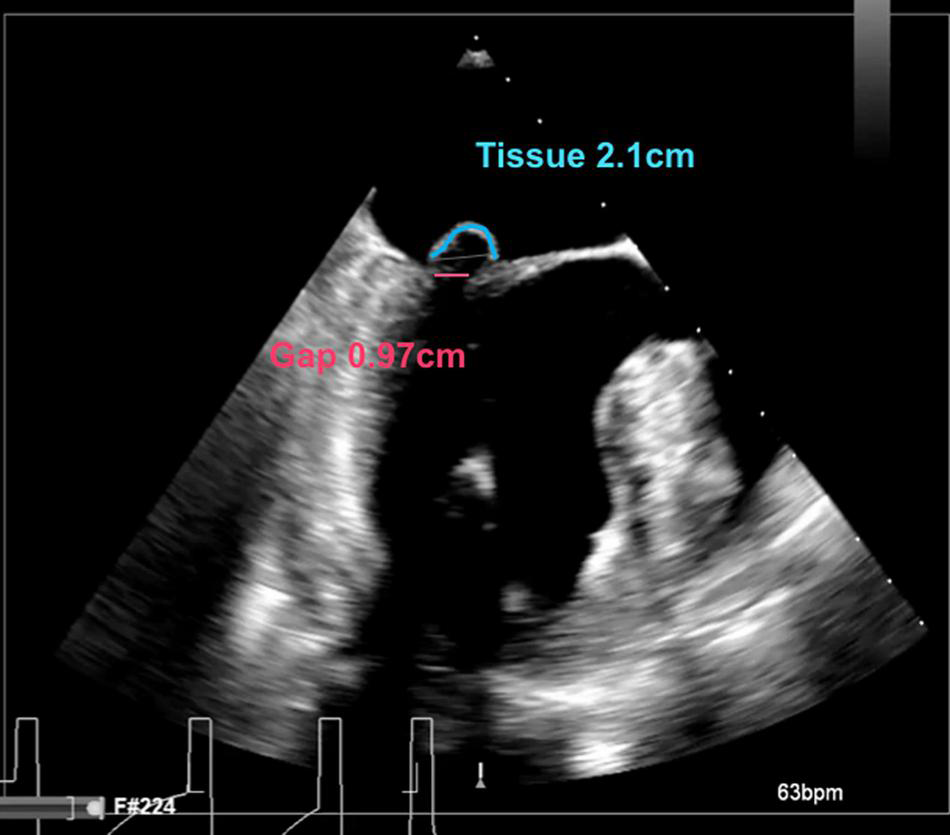

We report the selection criteria based on the current practice as applied in our center (Table 2). Patients are considered eligible for a Harpoon BHMVR procedure in case of severe DMR due to mid-segment pMVL (P2) prolapse, as determined on echocardiography. Although transthoracic echocardiography (TTE) is often used for the primary diagnosis, complementary transesophageal echocardiography (TEE) (e.g., with Philips EPIQ 7) including 3D clips is required to meticulously identify the mechanism of MR and extent of the prolapsing segment. In order to reduce MR without undue leaflet tension after cord implantation, the mitral leaflet coaptation surface needs to be sufficient. Sufficient coaptation is defined by a minimum tissue to gap ratio of 1.5:1, measuring the posterior prolapse segment length and the corresponding anteroposterior distance between the free edge of the anterior leaflet and the base of the prolapsed posterior leaflet segment (Figures 2, 3). Patients that have more extensive pMVL prolapse, with involvement of P1 and/or P3, and/or additional anterior leaflet prolapse are thus far not considered eligible for the procedure. Other major exclusion criteria are active endocarditis, left ventricular or left atrial appendage thrombus, severe mitral annular and/or leaflet calcification, mitral stenosis, functional MV disease, previous MV replacement surgery and a fragile or thinning apex. Patients with significant aortic or tricuspid stenosis or regurgitation requiring concomitant cardiac surgery are also not seen as optimal candidates for BHMVR with the Harpoon system.

FIGURE 2

Intraoperative long-axis TEE view showing part of the left atrium, the left ventricle and the left ventricular outflow tract, before repair with the HARPOON device. The measurement of the tissue/gap-ratio is demonstrated. Tissue-length (red), 2.1 cm; gap-length (blue), 0.97 cm. Tissue/gap-ratio = 2.1/0.97 = 2.2.